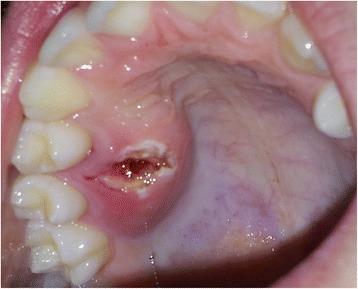

This report details the use of zygomatic oncology osseointegrated implants to support and retain a maxillary obturator in a 13-year-old male patient who underwent a right-sided hemi-maxillectomy (Brown Class 2b) (Brown and Shaw, Lancet Oncol 11:1001-8, 2010) for a myxoid spindle cell carcinoma. At the time of maxillary resection, two zygomatic oncology implants were inserted into the right zygomatic body and subsequently utilised to provide in-defect support and retention for a bar-retained maxillary acrylic obturator prosthesis, which restored the patient's aesthetics and function to a very high level. Close follow-up over 2 years demonstrated ongoing excellent function and disease control with no deleterious effects on facial or dento-alveolar growth clinically. This is the first clinical report of its kind in the published literature detailing the use of a zygomatic implant-retained obturator in a paediatric patient.

本报告详细介绍了在一名13岁男性患者中使用颧骨肿瘤骨整合种植体来支撑和固定上颌阻塞器的情况。该患者因黏液样梭形细胞癌接受了右侧半上颌骨切除术(Brown 2b级)(Brown和Shaw,《柳叶刀·肿瘤学》11:1001 - 8,2010年)。在上颌骨切除时,将两枚颧骨肿瘤种植体植入右侧颧骨体,随后用于为杆式固定的上颌丙烯酸阻塞器假体提供缺损内支撑和固定,该假体将患者的美观和功能恢复到了很高水平。超过2年的密切随访显示,功能持续良好且疾病得到控制,临床上对面部或牙牙槽骨生长无不良影响。这是已发表文献中首例详细介绍在儿科患者中使用颧骨种植体固定阻塞器的临床报告。